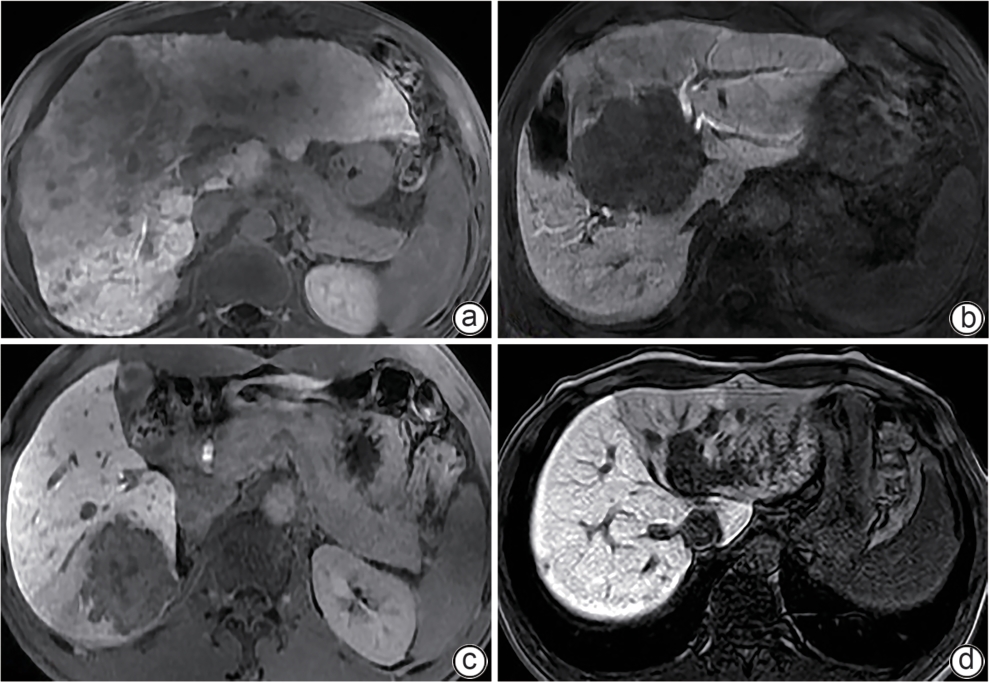

Application value of preoperative assessment of liver reserve function based on magnetic resonance cholangiopancreatography-related parameters and liver-to-muscle ratio in patients with hepatic space-occupying lesion

Yanhong YE, Lijian LU

2025, 41(9): 1845-1852. DOI: 10.12449/JCH250920

Abstract(335) HTML (107) PDF (2327KB)(45)

Abstract:

Objective  To establish a nomogram predictive model based on magnetic resonance cholangiopancreatography-related parameters and liver-to-muscle ratio, and to investigate the application value of this model in preoperative assessment of liver reserve function in patients with hepatic space-occupying lesion.  Methods  Clinical data and Gd-EOB-DTPA MRI imaging data were collected from 112 patients with hepatic space-occupying lesion who were hospitalized and scheduled for surgery in Wuming Hospital of Guangxi Medical University from April 2022 to April 2024. According to the degree of liver injury, the patients were divided into Child-Pugh class A group (65 patients with compensated liver function) and Child-Pugh class B+C group (47 patients with decompensated liver function, including 42 patients with Child-Pugh class B liver function and 5 patients with Child-Pugh class C liver function). The two groups of patients were measured in terms of liver-to-muscle ratio, relative signal intensity of the common bile duct, and bile duct score in different phases of contrast-enhanced CT scan, and univariate and multivariate Logistic regression analyses were used to identify independent predictive factors and establish a nomogram model. In addition, the receiver operating characteristic (ROC) curve, the calibration curve, and the decision curve were plotted to assess the discriminatory ability, accuracy, and clinical application value of the model. The independent-samples t test was used for comparison of normally distributed continuous data between two groups, and the Mann-Whitney U test was used for comparison of data with skewed distribution between two groups; the chi-square test was used for comparison of categorical data between two groups.  Results  There were significant differences between the two groups in liver-to-muscle ratio at 5 minutes (Z=-3.99, P<0.001), 10 minutes (Z=-4.39, P<0.001), 15 minutes (Z=-4.23, P<0.001), and 20 minutes (Z=-5.40, P<0.001) during the hepatobiliary phase, the relative enhancement degree of the common bile duct (Z=-4.85, P<0.001), and bile duct score (t=7.99, P<0.001). The multivariate Logistic regression analysis showed that liver-to-muscle ratio at 10 minutes during the hepatobiliary phase (odds ratio [OR]=0.63, 95% confidence interval [CI]: 0.44 — 0.90, P<0.05), liver-to-muscle ratio at 20 minutes during the hepatobiliary phase (OR=0.38, 95%CI: 0.17 — 0.82, P<0.05), and bile duct score (OR=0.17, 95%CI: 0.07 — 0.39, P<0.05) were independent influencing factors for the preoperative diagnosis of liver function decompensation. The nomogram model established based on liver-to-muscle ratio at 10 minutes during the hepatobiliary phase, liver-to-muscle ratio at 20 minutes during the hepatobiliary phase, and bile duct score had an area under the ROC curve of 0.905 (95%CI: 0.849 — 0.960), with a sensitivity of 78.7% with a specificity of 89.2%.  Conclusion  The nomogram model established based on the liver-to-muscle ratio at 10 and 20 minutes during the hepatobiliary phase and bile duct score can effectively assess the status of liver reserve function in patients with hepatic space-occupying lesion before surgery.